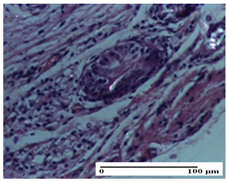

| Dermo-hypodermic collagenization, mild inflammatory infiltrate (S1, G0) | dermal collagenization (S0, G0) | dermal collagenization, rare inflammatory elements—detail in polarized light microscopy (S1, G0, D0) |